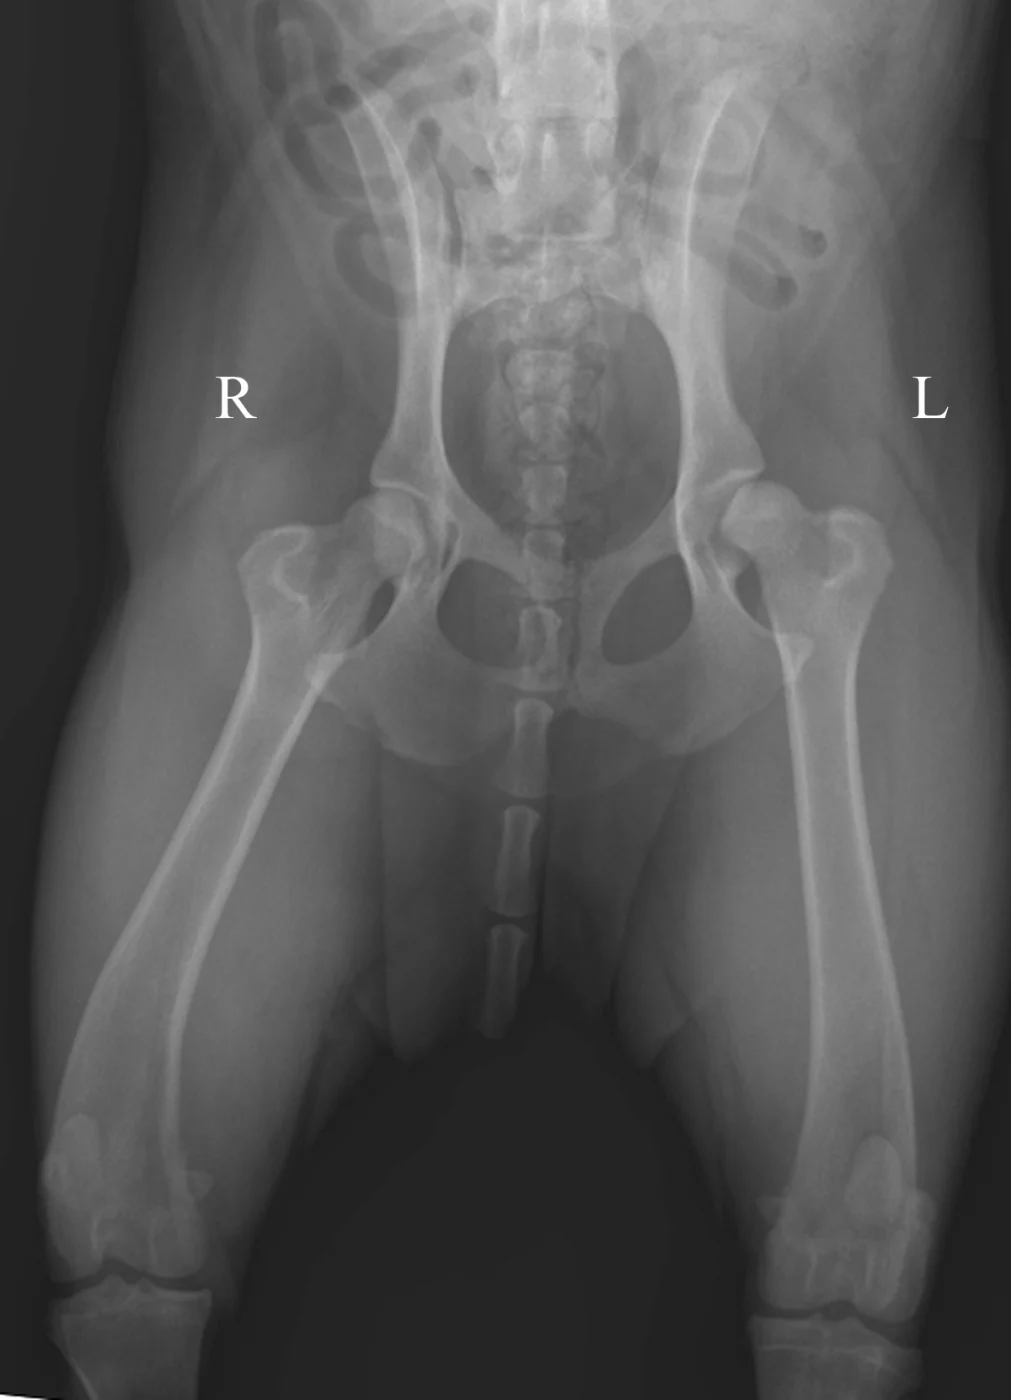

Figure 1A demonstrates the normal positioning for the ventrodorsal hip-extended view (the view that should be submitted to the Orthopedic Foundation for Animals). This view is best obtained with the dog placed in dorsal recumbency, which is done by using a foam positioning trough. All but the pelvis and hindlimbs are within the trough. While in a flexed position, the limbs are internally rotated and abducted so that the stifles are almost touching. The limbs are then extended, maintaining the internal rotation, until the femurs are parallel with the table.

If the stifles are kept internally rotated, the patella should be centrally located over the distal femurs, as seen in the normally positioned radiograph (Figure 1B). In this image the femurs are parallel with each other and parallel with the imaging plate. Note the uniform and equal size of the obturator foramen on this well-positioned radiograph. Ideally, the sacrum, ilial wings, and entire 7th lumbar vertebra should be included in the image. Figure 1C shows an example of the pelvis correctly positioned.